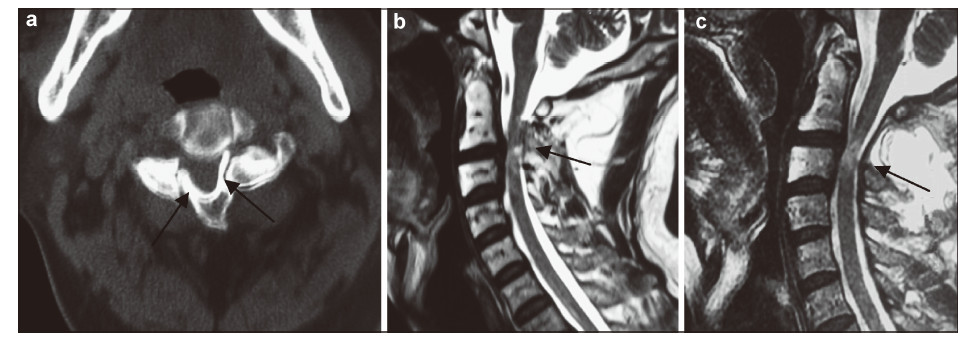

| Figure 4 A 45-year-old man presented with bilateral C3 spondylolysis.(a) Axial CT scan revealed well‐corticated clefts between the bilateral C3 facets (arrows).(b) On sagittial MRI,the canal at the spondylolytic level was narrow and the subarachnoid space disappeared (arrow).(c) Follow‐up MRI showed the subarachnoid space was clear (arrow). |